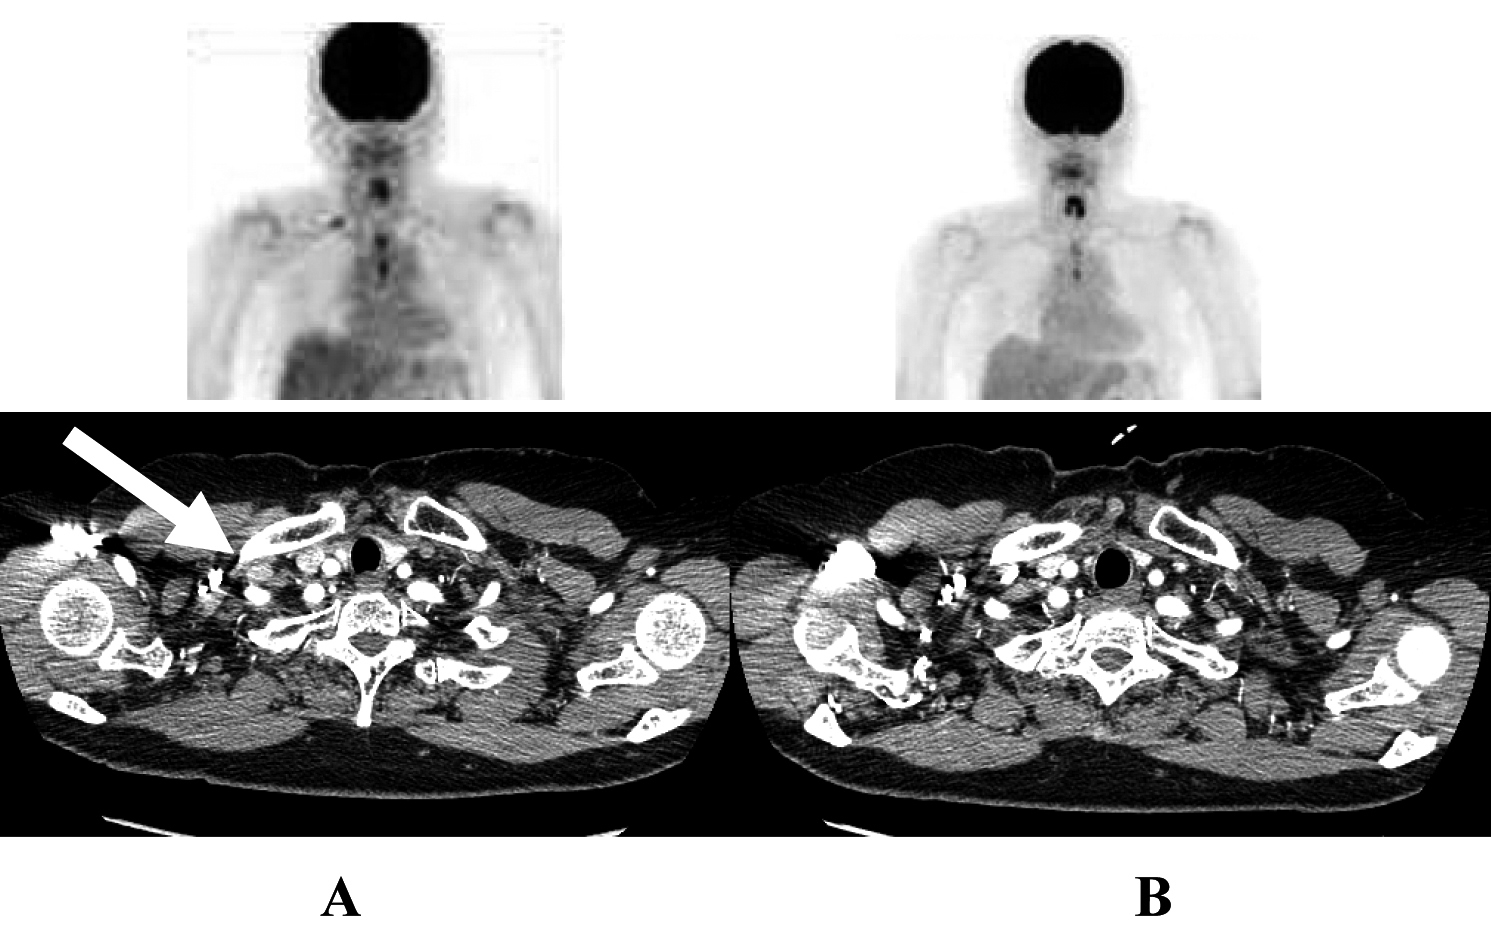

A 70-year-old woman was referred to our hospital in October 2007 because of chest discomfort and anterior mediastinal mass on chest computed tomography (CT) (Fig. 1A). Percutaneous CT-guided biopsy was performed and the lesions were confirmed histologically to be epidermoid-type thymic carcinoma. She was treated with 4 cycles of a combination of cisplatin (50 mg/m2) and doxorubicin (40 mg/m2) on day 1, vincristine (0.6 mg/m2) on day 3, and cyclophosphamide (700 mg/m2) on day 4 (ADOC chemotherapy), and showed partial response to the treatment (Fig. 1B). Subsequently, the residual tumor was surgically resected in March 2008, followed by a total of 60 Gy (2 Gy × 30 days) thoracic radiotherapy. In October 2009, positron emission tomography (PET) and chest CT scan revealed right clavicular lymph node swelling (Fig. 2A). Although biopsy was not performed, this was considered relapsed thymic cancer. She was retreated with modified ADOC chemotherapy using nedaplatin (80 mg/m2) instead of cisplatin because of her reduced renal function (creatinine clearance < 50 ml/min). After 4 cycles of modified ADOC, the patient showed a complete response (Fig. 2B). As of October 2011, the patient is still alive without any symptoms or further recurrence.

![]() Click for large image | Figure 2. The response to second-line ADOC chemotherapy in case 1. Chest computed tomography and positron emission tomography before initial ADOC chemotherapy (A) and after four cycles of second line ADOC chemotherapy (B). |